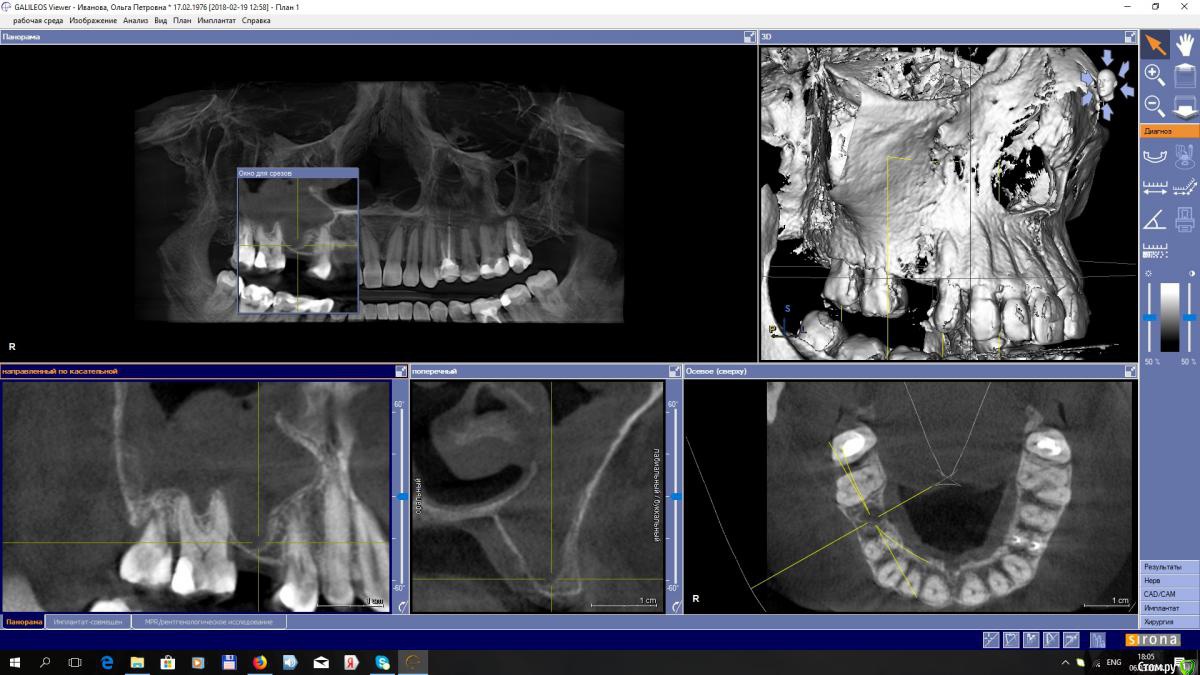

EEcho Опубликовано 7 марта, 2018 Поделиться Опубликовано 7 марта, 2018 Доброго времени суток. 3 месяца назад пациентка обратилась с целью поставить имплант в области 15.На КТ нарисовалась такая картинка, инородное тело и возможен гайморит без жалоб. была направлена к ЛОР. ЛОР сделал ревизию.прошло 2 месяца , сделали повторный КТ и сейчас картина такая. Что делать, ждать или отправить опять к ЛОР, или что-то можно уже делать? Ссылка на комментарий